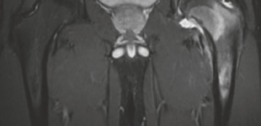

Standard anteroposterior (AP) pelvis and lateral hip radiographs are often the initial diagnostic step, but they may only show non-specific regional osteopenia or subtle cortical thickening in intra-articular cases.

High-resolution, thin-slice computed tomography (CT) with multiplanar reconstruction is the gold standard for defining the osseous anatomy. The CT scan accurately delineates the nidus as a well-circumscribed, radiolucent focus, often containing a central fleck of mineralization, surrounded by varying degrees of sclerosis. The surgeon must meticulously map the location of the nidus relative to reliable arthroscopic landmarks, such as the medial synovial fold, the zona orbicularis, and the articular margin of the femoral head.

Magnetic resonance imaging (MRI) is highly sensitive for detecting the profound bone marrow edema and adjacent soft tissue inflammation characteristic of osteoid osteomas. While MRI may obscure the nidus itself due to the overwhelming edema signal, it is invaluable for assessing the extent of reactive synovitis, evaluating the integrity of the articular cartilage, and identifying concurrent labral pathology.